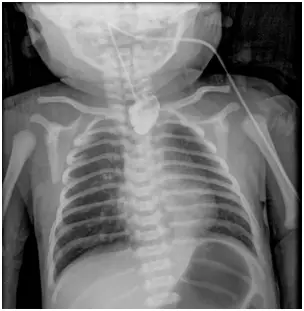

一名 33週的早產兒,出生後生命徵象穩定,但在第一次餵奶時發現有咳嗽、嗆到、發紺的狀況,且伴隨著大量口水流出;當試著置入胃管時,發現無法放至胃部,因此新生兒科醫師安排食道鋇劑攝影如圖。針對上述情況,下列相關敘述何者錯誤? 圖片描述

從胸腹部平片可見:

1. 餵食管鞘(nasogastric tube)在頸部/胸腔內彎曲盤繞,停留在上段食道盲袋處,無法進入腹腔,符合食道閉鎖的表現 (en.wikipedia.org)。

2. 腹部出現空腸氣體(distal bowel gas),顯示遠端食道與氣管間有交通;空氣經由氣管—食道瘻管進入胃腸道 (radiologykey.com)。

綜合上述,典型符合 Gross 分類 type C(proximal EA + distal TEF)。